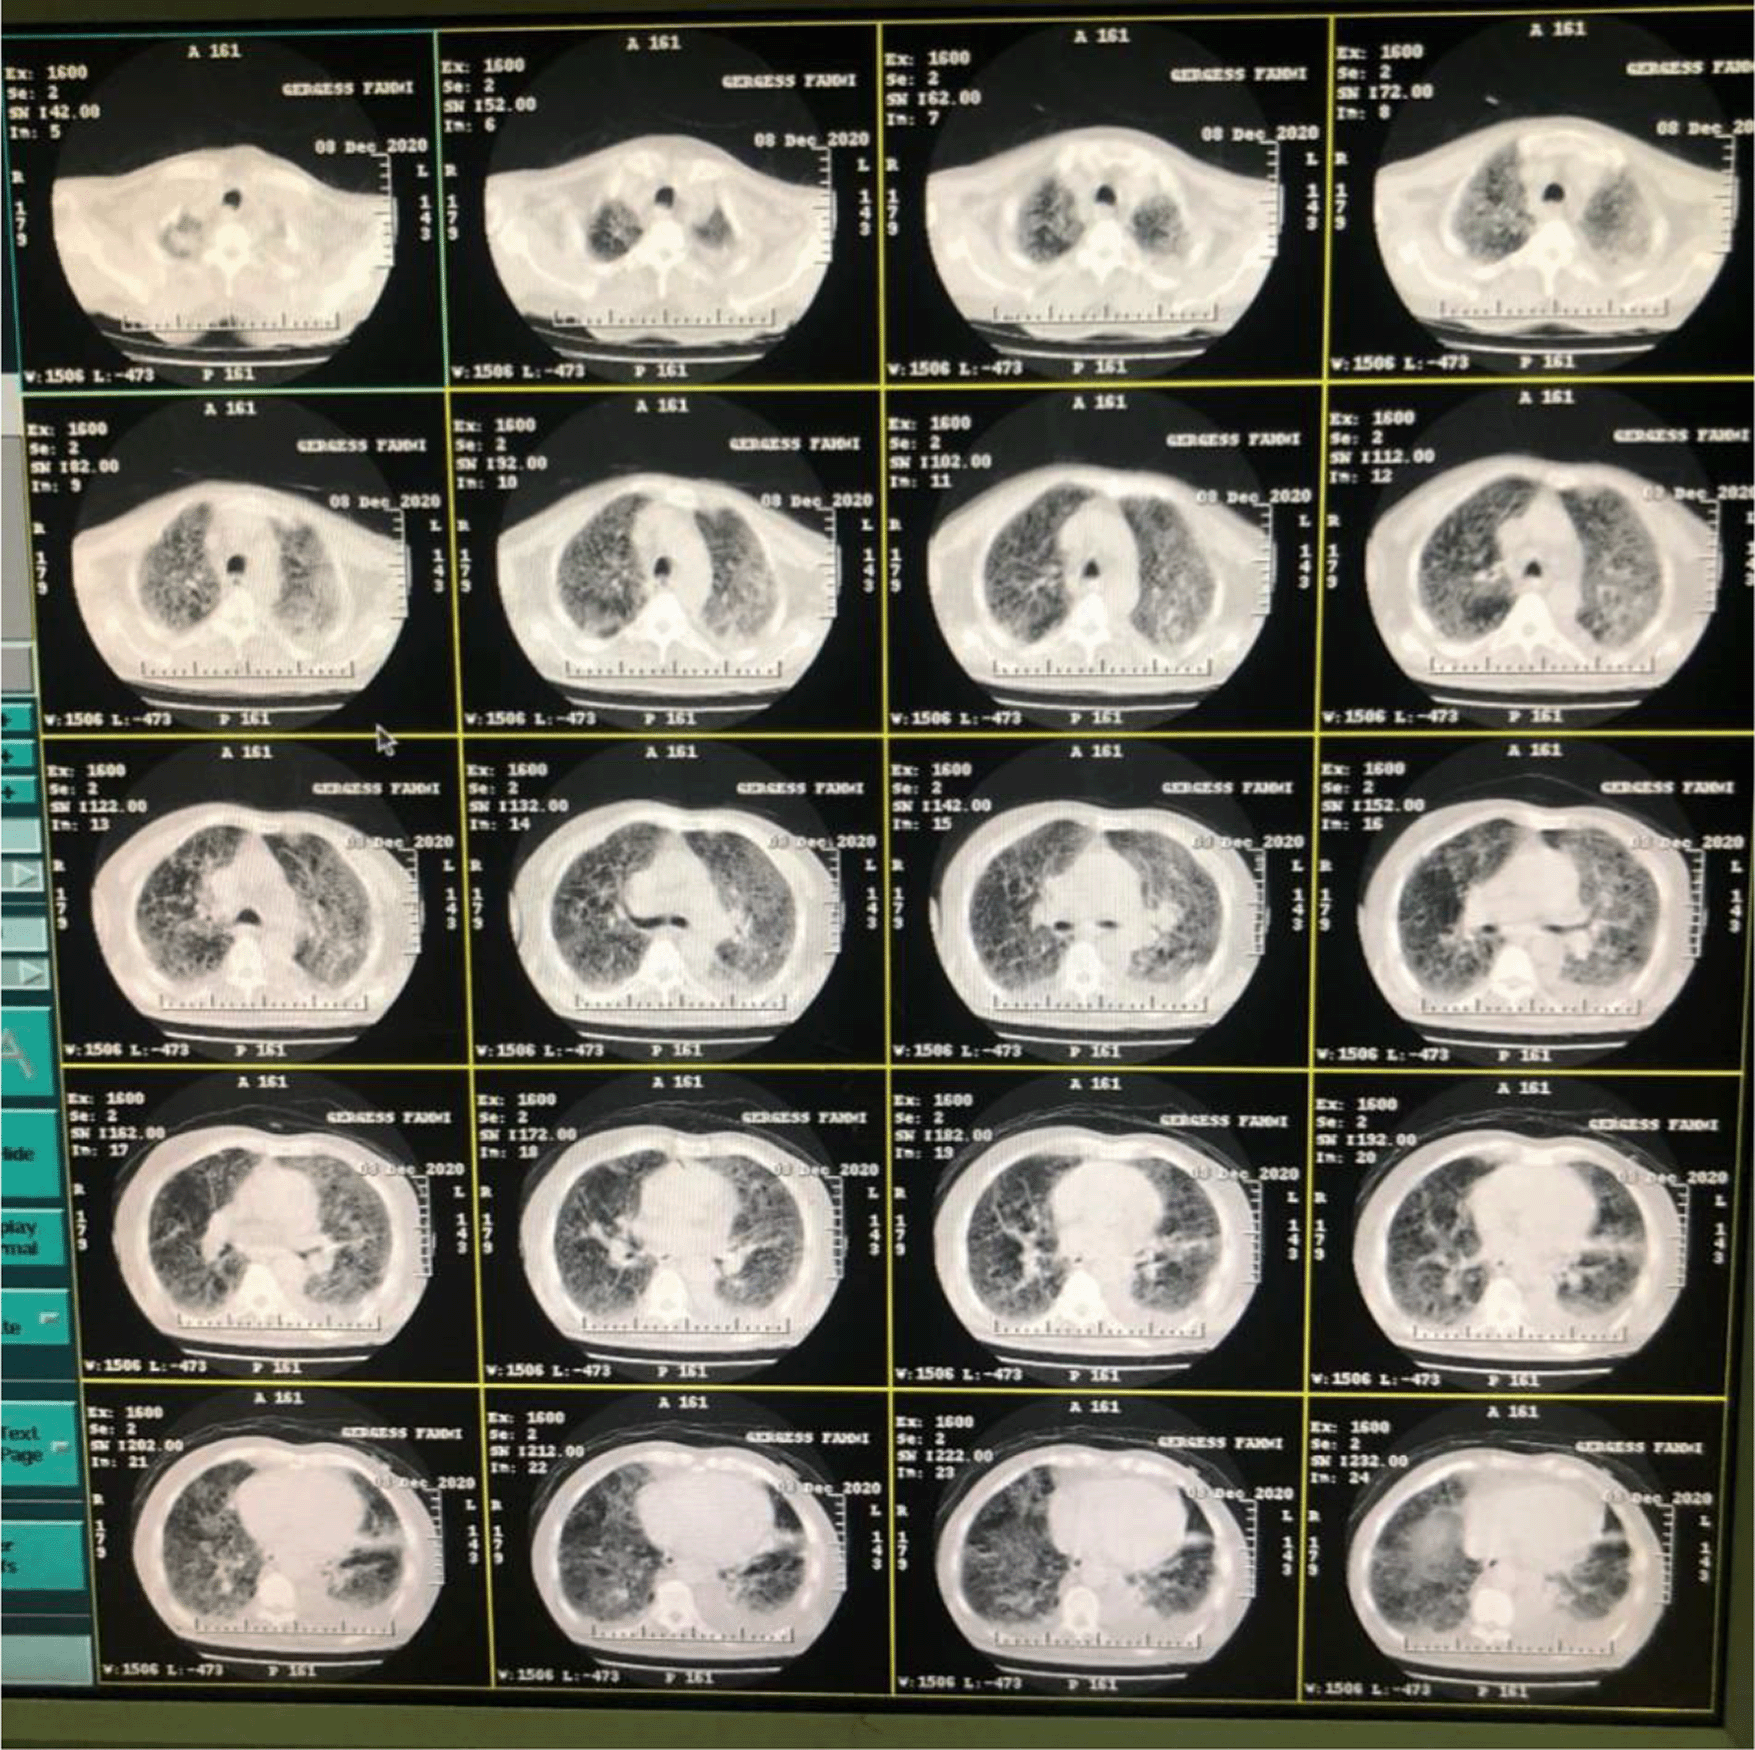

Chest computed tomography was done for the patient on the first day of hospital arrival, 8 December, shown in Figure 1.

Figure 1. Chest computed tomography of case 1 on hospital arrival.